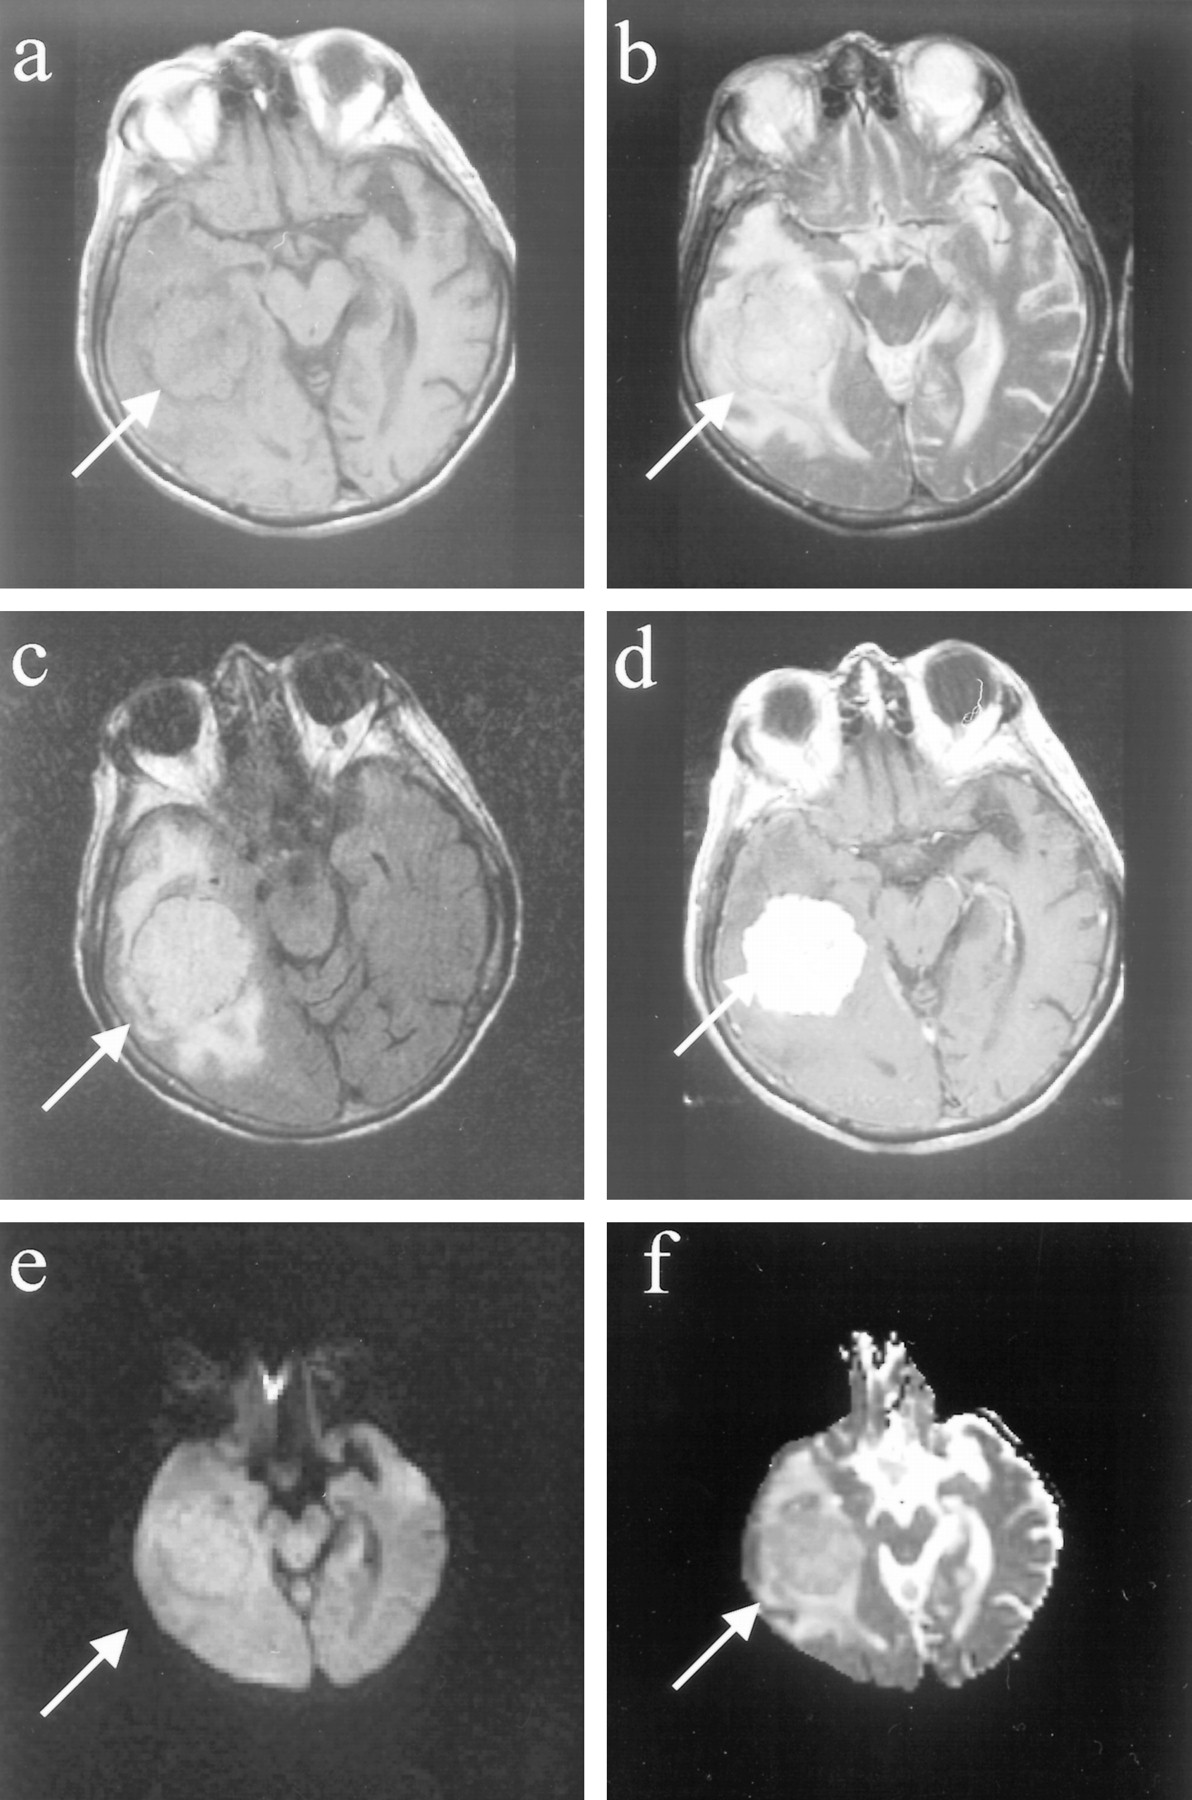

Images of patient (patient 4 in the Table) with a malignant meningioma (WHO grade III).

A, Axial T1-weighted image (500/12/1) shows a well-marginated, recurrent extraaxial mass in the parietal convexity.

B, Axial fast spin-echo T2-weighted image (3000/84/1) of this recurrent meningioma appearing isointense to cortex.

C, Axial fast fluid-attenuated inversion recovery image (10002/162/1) shows isointense mass with smooth borders at resection site and no evidence of brain invasion.

D, Contrast-enhanced spin-echo T1-weighted image (450/12/1) shows smooth, homogeneous enhancement and dural enhancement typical of meningiomas.

E, Diffusion-weighted image (10000/99/1) of the recurrent meningioma, which is hyperintense (lightbulb).

F, Meningioma is hypointense on the ADC map, and the Dav was extremely low (0.45 × 10−5 cm2/s).